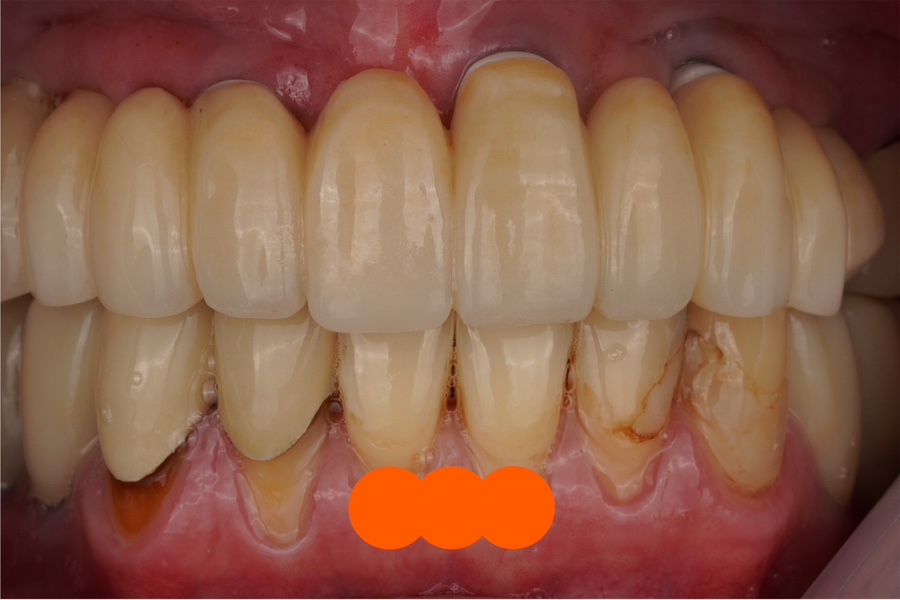

수리 완료

치료 후 환자분께서도 감쪽같다며

거울로 계속 앞니를 살펴보시더라고요

보시다시피 깨진 부위와

수리해드린 부위 경계가 티나지않게 잘 됐고

색상의 그라데이션도 자연스럽게

주변 치아와 유사하게 잘 재현되었죠.

강도가 문제인데, 아무래도 도자기나

지르코니아에 비해서

레진은 강도가 약할수밖에 없는데요

그렇다고 저부분때문에

전체 보철을 다 새로 만들 수도 없는 노릇이니

이런 브릿지 보철물에 있어서는

한두개 치아 수리하는 건 합리적인 선택지라고

저는 그렇게 생각합니다.

물론 해드릴때 잘 해드리는게 중요하죠.

티나지않게 말입니다.

치료기간 2024.04.28. 당일